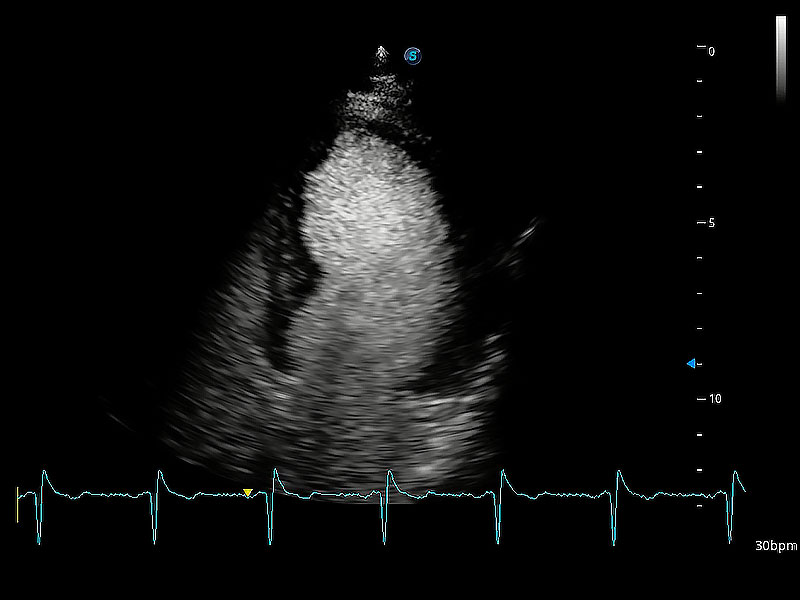

ProPet 80 配備了豐富的心臟探頭群、先進(jìn)的成像技術(shù)和專業(yè)的心臟測(cè)量工具,可幫助動(dòng)物醫(yī)生為不同體型和生理結(jié)構(gòu)的動(dòng)物提供心臟和心肌功能的全面評(píng)估。

通過(guò)360度任意調(diào)節(jié)3條M型取樣線,在同一心動(dòng)周期上觀察心臟不同位置的運(yùn)動(dòng)曲線,得到準(zhǔn)確的心功能測(cè)量數(shù)據(jù),有效評(píng)估心肌運(yùn)動(dòng)及左心室功能。